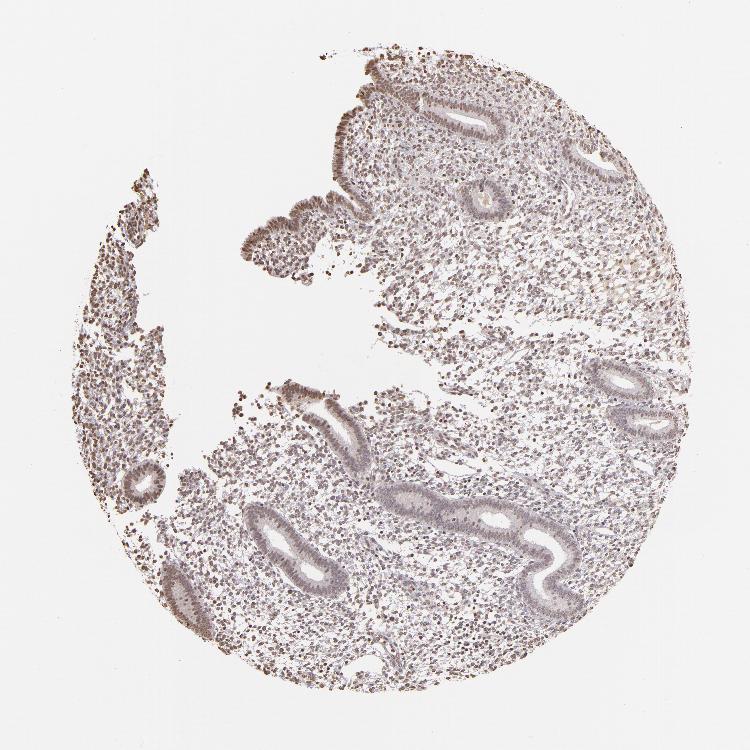

ENDOMETRIUM 1 - Antibody stainingi

Antibody staining in the annotated cell types in the current human tissue is reported as not detected, low, medium, or high, based on conventional immunohistochemistry profiling in selected tissues. This score is based on the combination of the staining intensity and fraction of stained cells.

Each image is clickable and will lead to virtual microscopy that enables deeper exploration of all samples and also displays staining intensity scores, fraction scores and subcellular localization as well as patient and tissue information for each sample.

Antibody CAB002008Antibody CAB002009

Cells in endometrial stroma Not detectedLow

Glandular cells Not detectedLow